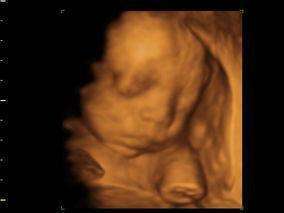

妊娠时间在24周到36周的8名女婴和7名男婴进行了扫描。这些胎儿的发育速度相同。在妊娠初期,胎儿会触摸头部上部和两侧,妊娠晚期开始触碰更敏感的下部,面部部分区域和口部。

到了第36周,绝大多数胎儿在触碰口部前会张开小嘴,科学家表示这说明他们预感到触摸。健康发育的胎儿口部周围区域会随着时间的推移敏感度提高,他们进一步感知到口部的动作。

在吮吸拇指或者其他手指前张开小嘴说明胎儿已经明白自己的意图。观察到连续的动作,说明胎儿已经发育成熟。这种能力是出生后开始新生活的基础。